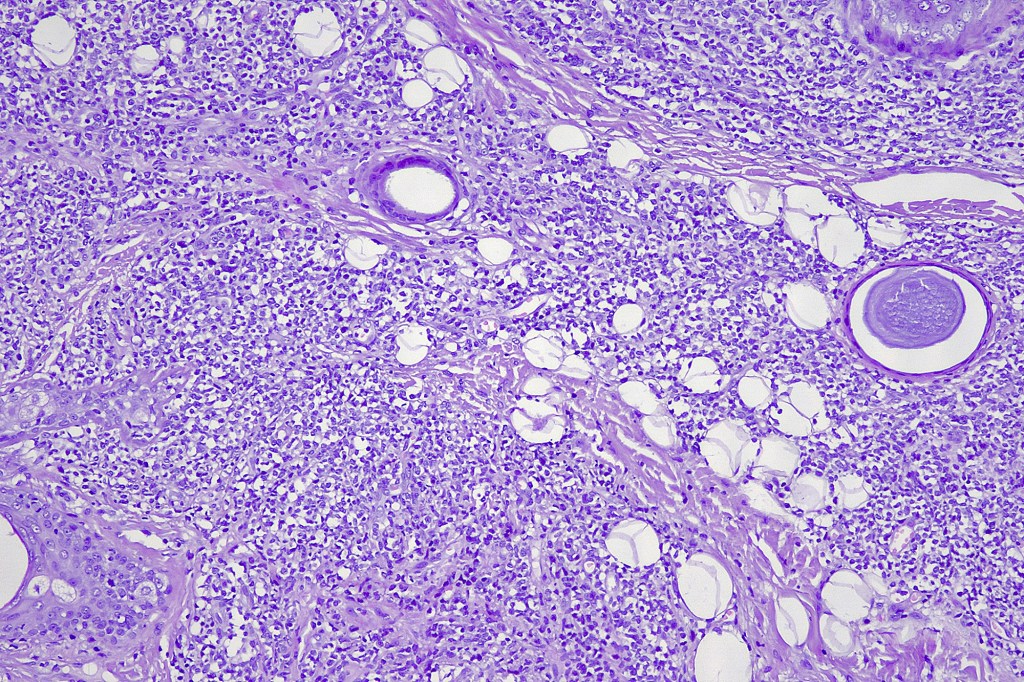

. Monotonous blast cells with gray-blue cytoplasm & irrregular vesicular nuclei with prominent nucleoli

. CD4, CD43, CD56, CD123, CD303, TCF4 & TCL1 +ve

. Variable CD68, CD7, CD33 & TdT +ve

. CD34, MNDA, lysozyme & myeloperoxidase -ve.